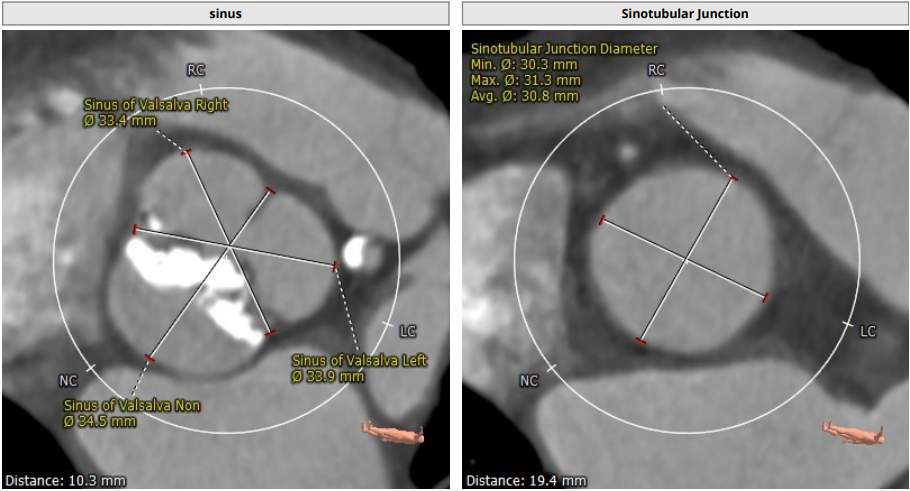

主动脉根部:

Annulus:23.3 mm,LVOT:21.9 mm,STJ:30.8 mm,Asc.AO:43.5 mm

TYPE1 型二叶瓣,重度钙化,钙化呈单边分布,主要集中在无冠窦侧,左右可见非钙化脊,左冠高度约 13.2 mm,右冠高度约 14 mm,法式窦结构大,STJ 高度约 19.4 mm、直径约 30.8 mm,升主动脉可见增宽,最宽处约 47.1 mm,心脏角度约 46°,左室大小可,右窦居中体位:RAO4°、CAU21°,左冠切线位:LAO2°、CAU16°。